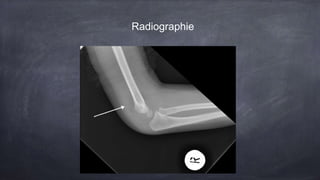

Une fille de 4 ans présente une douleur au coude suite à une chute, ne voulant pas utiliser son bras. Les examens révèlent une douleur à la flexion et une possible fracture, notable par la présence d'un fat pad postérieur sur la radiographie, indiquant une fracture jusqu'à preuve du contraire. Un suivi en orthopédie est recommandé dans les 7 à 10 jours suivant une immobilisation temporaire.